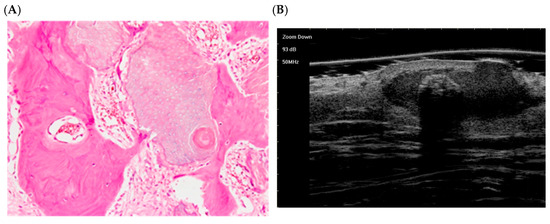

10. Pilomatricoma: Histological Morphological Stages

- In the early stage, the lesion appears as a small cyst with internal fissuring, filled with keratin and ghost (shadow) cells, and surrounded by a peripheral layer of basaloid cells.

- In the fully developed stage, larger eosinophilic keratin masses containing numerous shadow cells are surrounded by a mantle of active peripheral basaloid cells [58].

- The regressive stages are marked by loss of basaloid epithelium:

- In the early regressive stage, residual basaloid aggregates persist at the periphery, with central shadow cells, inflammatory infiltrate, and multinucleated giant cells.

- In the late regressive stage, the tumor becomes an amorphous keratinized mass (often calcified/ossified), with very few viable cellular elements [58].

- Li, L.; Xu, J.; Wang, S.; Yang, J. Ultra-High-Frequency Ultrasound in the Evaluation of Paediatric Pilomatricoma Based on the Histopathologic Classification. Front. Med. 2021, 8, 673861. [Google Scholar] [CrossRef]